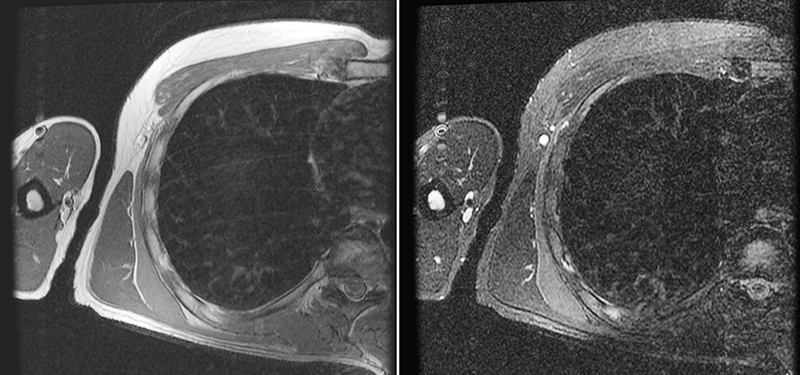

Pneumopathie en rapport avec la COVID-19